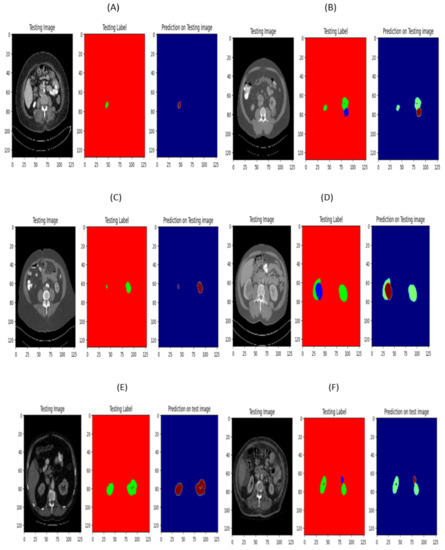

3.2.4. Prediction on Testing Images

An example of segmenting the kidney and a kidney tumor utilizing the Seresnet50, Seresnet101, and Seresnet152 models is shown in Figure 9 using test images. The annotation images annotate the kidney and tumour regions in green and brown. The performance of the segmentation model is assessed using these annotations as the source of truth. On the other hand, the segmentation predictions for the kidney and tumor in the outcome images are visible. These photos clearly show the segmentation outputs of the Seresnet50, Seresnet101, and Seresnet152 models, demonstrating their effectiveness in locating and defining kidney and tumor regions inside CT scans.

Figure 9.

(A) seresnet50 image normal and (B) seresnet50 image with tumor. (C) seresnet101 image normal and (D) seresnet101 image with tumor. (E) seresnet152 image normal and (F) seresnet152 image with tumor.